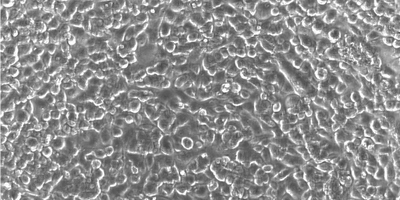

Scientists at Cincinnati Children's use stem cells to grow connected, functioning set of miniature human liver, pancreas, and biliary ducts